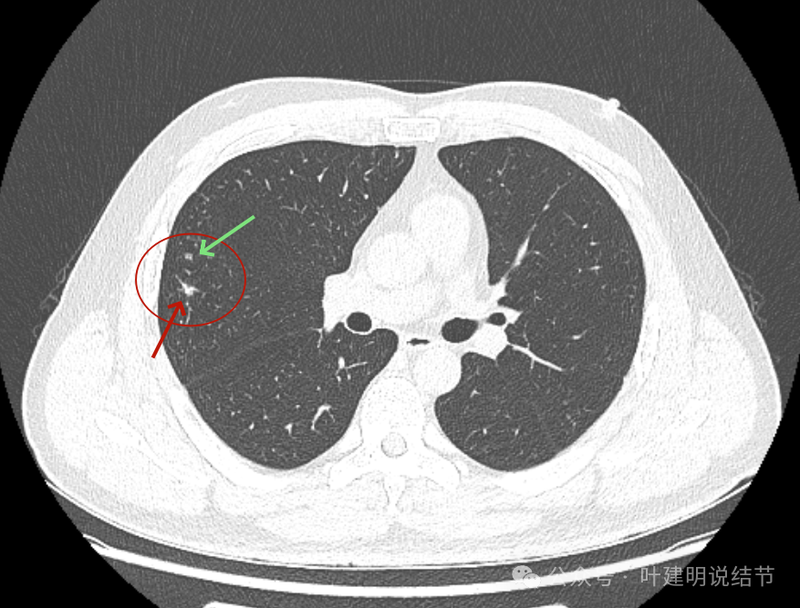

右上叶实性结节,边缘不光滑,有血管征,内部密度稍不均,整体轮廓较为清楚。

主病灶冠状位见血管紧挨,膨胀性不够。

主病灶矢状位见病灶略显模糊,边缘相对较为平直。

主病灶连续层面影像:

病灶出现,密度稍高。

密度高,表面不平不光滑,边上有小的点状高密度的卫星灶似的。

血管征明显。

边缘区显得毛糙。